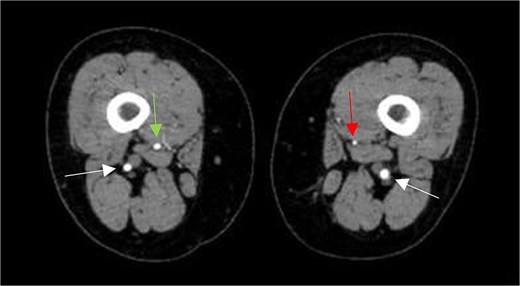

Axial CTA image shows hypoplastic left SFA along its course in the adductor canal (vertical arrow on left leg), but normal-sized right SFA (vertical arrow on right leg), and bilateral prominent PSAs (horizontal arrows).